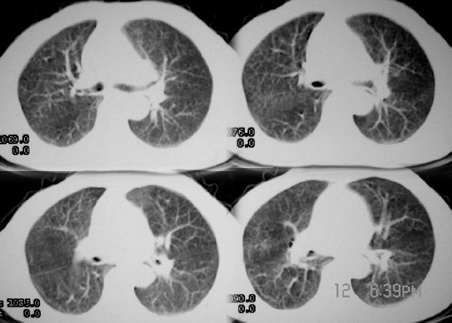

女,80岁。因咳嗽,声音嘶哑1月

影象表现:左上肺纵隔旁可见一形态略不规整的软组织肿块(上自主动脉旁,下至左肺动脉上层面);

密度较均匀;最大层面与主动脉弓呈宽基底,但与其可见一线状低密度影分割,下方与尖后段

支气管内侧壁和左上肺静脉分界不清(尖后段支气管未见明显狭窄)双肺血管纹理明显增多

以右侧明显并可见胸膜下线 不规则线状影和中叶的斑片状影;左膈明显升高。

临床表现:老年女,80岁。以咳嗽,声音嘶哑1月为主诉。

影象诊断:考虑纵隔型肺癌伴纵隔淋巴结转移.肺内炎变待除外.肺内转移建议hrct

病灶和主动脉弓是宽基底相连,但与主动脉弓壁之间的脂肪间隙清晰可见;肺窗示病灶边缘有不规则毛刺样;左肺叶段肺气肿;左侧横膈升高。右肺中叶炎变;结合病史考虑纵隔型肺癌可能性大。其他的难说!

左上肺纵隔旁可见一形态略不规整的软组织肿块,与主动脉弓壁之间的脂肪间隙清晰,肺窗示病灶边缘有不规则毛刺样改变,右肺中叶炎症。综合病史考虑纵隔型肺癌。